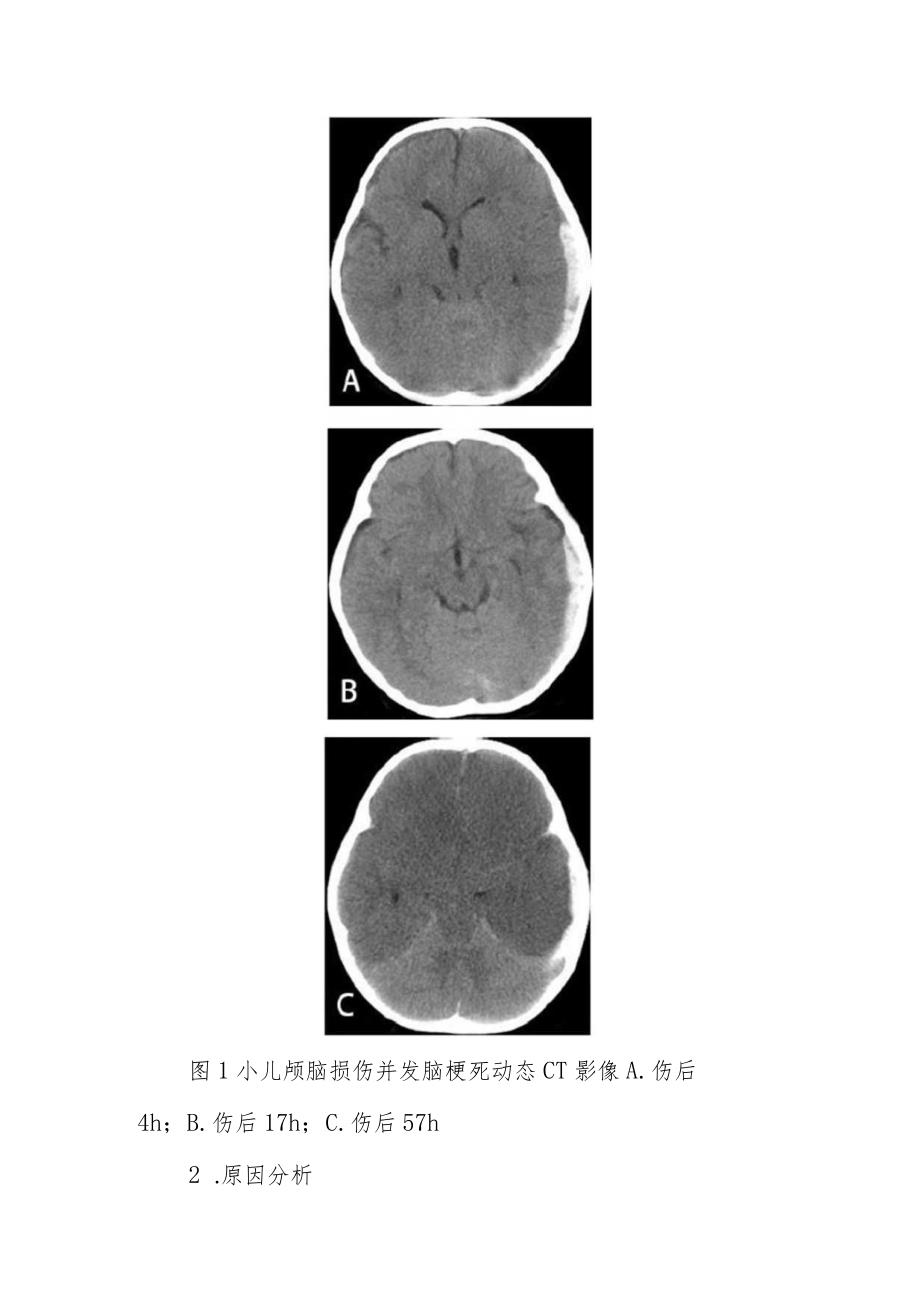

2、后胆囊,肝、脾、胰、双肾声像图未见明显异常,腹腔未探及积液。入院后给予止血、脱水、营养神经、吸氧、心电监护等治疗。7月4日复查头颅CT示血肿无明显增多。7月5日,患儿出现频繁抽搐,给予安定静滴控制抽搐。7月6日凌晨1点50分出现双侧瞳孔散大;头颅CT示双侧额题顶大面积脑梗死。家属放弃治疗,自动出院。图1小儿颅脑损伤并发脑梗死动态CT影像A.伤后4h;B.伤后17h;C.伤后57h2 .原因分析小儿脑血管内膜发育不完善,如果颅内压增高,会压迫血管,引起血管闭塞而导致脑梗死。血性脑脊液使血管痉挛。小儿脑组织饱满,颅内代偿空间小。出血后导致患儿出现频繁抽搐。3 .治疗体会因为目前GCS评分未考虑年龄因素,小儿GCS评分不能与成人等同,如果小儿(小于3岁)的GCS评分与成人相同,小儿应该考虑病情更重,对小儿颅脑损伤一定不能掉以轻心。预防外伤性脑梗死最重要的还是降低颅内压,因此对去骨瓣减压术的指征应该更宽一些,可以遵循“宁过勿不及”的原则。用药上应尽早应用钙离子拮抗剂的药物。补足液体量,小儿对脱水非常敏感。及时控制癫痫大发作,防止缺氧的进一步加重。因为一旦发生大面积脑梗死,将是致命的,所以对脑外伤性脑梗死重在预防,尽量将各种工作做到前面。